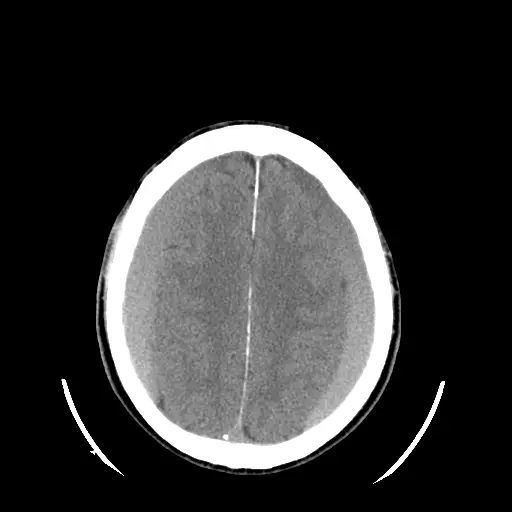

78歲女性,主訴一週以來步態不穩且頭痛。未注射顯影劑的頭部電腦斷層影像如圖,最可能的診斷為何?

CT影像可見雙側大腦半球頂蓋區緊貼腦表面之扁平crescent形異常濃度影,並沿半球凸面廣泛分布,呈現與皮質灰質相似或略低之同質密度;左右兩側均有,且可見影像跨越縫線下方而達對側(未受縫線限局)。未見典型經硬膜骨板下之lens狀凸起,亦無基底池或腦溝之血腫跡象。此影像符合亞急性期(約3–14天)subdural hematoma之同質iso‐dense或輕度低密度特徵,且形狀crescent、可跨縫線,並非lens狀或佔據腦溝,排除epidural hematoma及subarachnoid hemorrhage。此外,缺乏任何明顯的腫塊邊緣及硬腦膜尾(manifest dural tail),亦不支持meningioma。